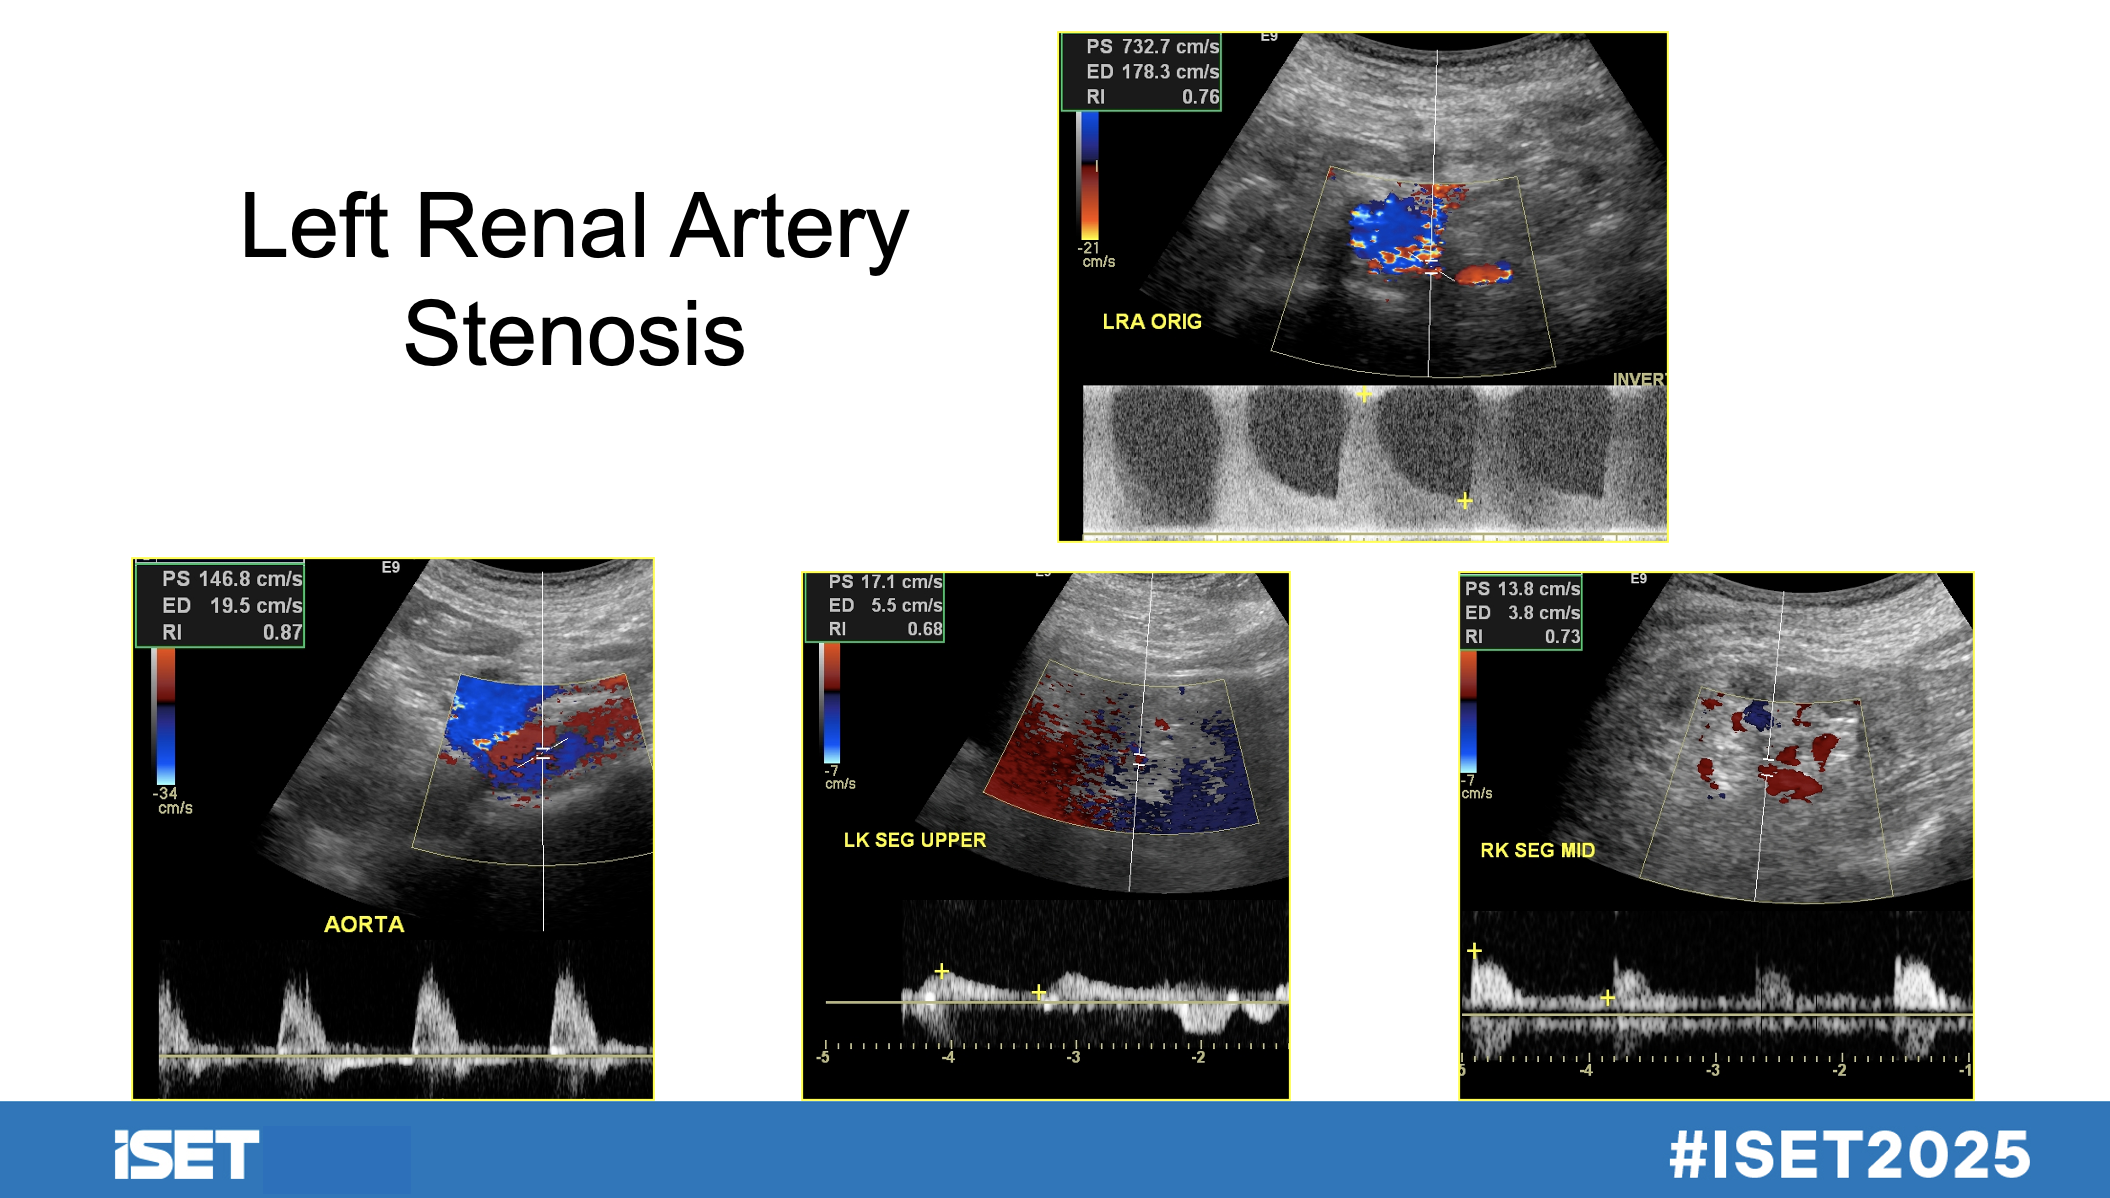

Dr. Pellerito outlined the key Doppler ultrasound criteria for diagnosing renal artery stenosis:

- Peak systolic velocity (PSV) >200 cm/sec

- Renal-aortic ratio >3.5

- Abnormal segmental artery waveforms, including tardus-parvus waveforms characterized by a delayed systolic upstroke and absence of an early systolic peak.